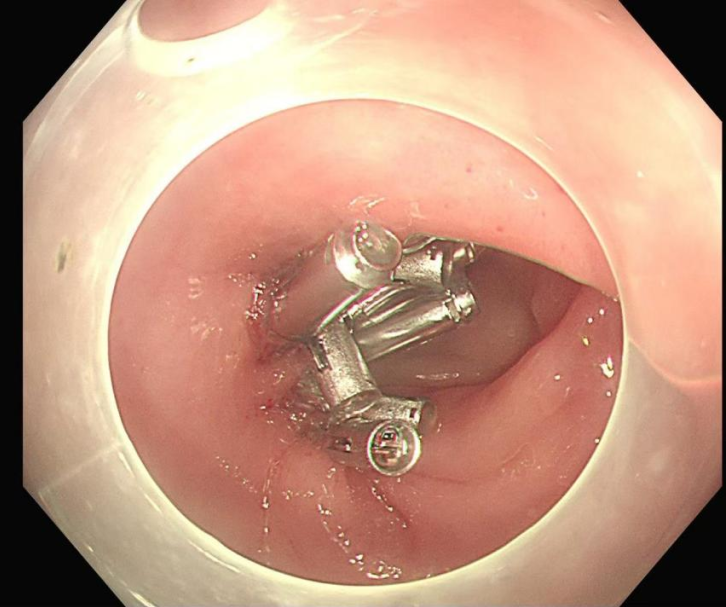

手术过程中,申星杰教授与医院内镜团队密切配合,操作精准高效,仅用 30 分钟便一次性完整切除张女士直肠黏膜病变部位。术后,张女士病情稳定,未出现任何手术相关并发症,目前恢复状况良好。

图解手术过程